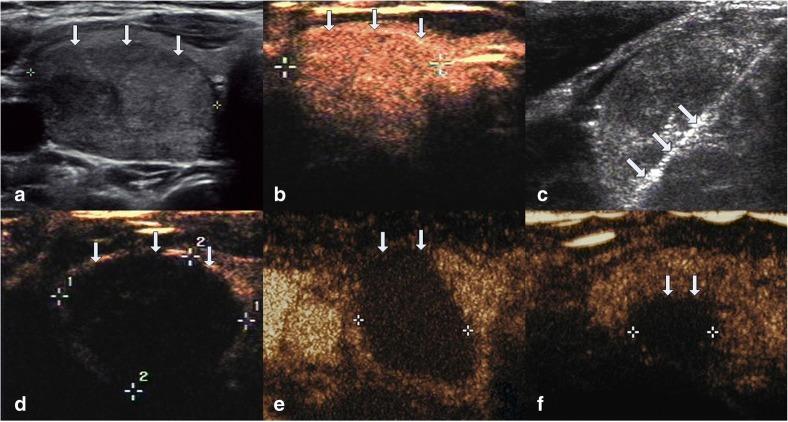

This retrospective study evaluated 194 non-functioning solid benign TNs of 103 patients. The TNs were categorized as small (≤5 ml), medium (5.1 to 13 ml), intermediate (13.1 to 30 ml) and large (over 30 ml) according to the initial volume of TNs before ablation. Clinical evaluation and contrast-enhanced ultrasound (CEUS) were carried out before ablation and the follow up at 1, 3, 6 months and every 6 months after ablation. All patients were asked to assess the cosmetic score (1-4 scores) and symptom score (0-10 scores) before ablation and every follow up after ablation.

All patients underwent RFA without any major complications. The mean treatment sessions were 1.5 ± 0.6. 98 nodules required a single session (98/194, 50.5%), 87 required two sessions (87/194, 44.9%), 9 required three sessions (9/194, 4.6%). The average follow up months were 16.3 ± 5.6 (range, 6-24 months) and no nodule regrew in our study. After RFA treatment, the TNs volume significantly decreased (P < 0.001). The small group of nodules shrunk larger compared to the medium, intermediate and large groups (P < 0.001). Cosmetic signs and pressure symptoms were significantly improved, particularly in the intermediate and large groups (P < 0.05).

RFA is effective for treating non-functioning solid benign TNs and controlling clinical symptoms with a low complication rate during 2 years follow up. The reduction rate was related to the initial volume of nodules. Patients were satisfied with cosmetic signs and pressure symptoms improvement, particularly in the intermediate and large groups. However, multiple RFA treatments should be used in larger nodules to achieve the desired clinical outcomes.

方法

所有患者均顺利完成 RFA 治疗,无重大并发症。平均治疗次数为 1.5±0.6 次。98 个结节(98/194,50.5%)需单次治疗,87 个结节(87/194,44.9%)需 2 次治疗,9 个结节(9/194,4.6%)需 3 次治疗。平均随访时间为 16.3±5.6 个月(6-24 个月),研究期间无结节复发。RFA 治疗后,TN 体积明显缩小(P<0.001)。与中、大组相比,小组结节的缩小更为明显(P<0.001)。美容体征和压迫症状显著改善,尤其是中、大型结节(P<0.05)。

RFA 治疗非功能性实性良性 TN 效果显著,2 年随访期间并发症发生率低,可有效控制临床症状。缩小率与结节的初始体积有关。患者对美容体征和压迫症状的改善较为满意,尤其是中、大型结节。然而,为了达到理想的临床效果,较大的结节应采用多次 RFA 治疗。